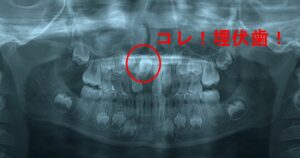

6

口腔外科専門医との

緊密な連携

月に一度、口腔外科専門医が来院。

抜歯や埋伏歯処置など、難しい症例でも院内で対応できる高度な医療体制を整えています。